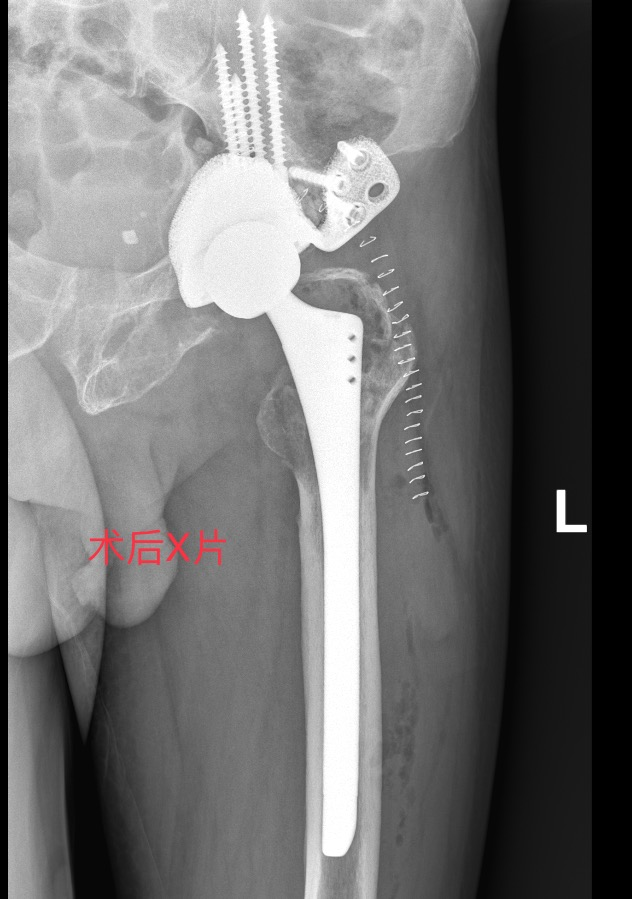

从卧床到康复仅24小时!

实现科技与医术的完美融合

曾爷爷的康复速度令人惊叹!

从卧床不起到行动自如

仅仅花了24 小时!

麻醉苏醒后,曾爷爷的髋关节已能无痛自由屈伸;术后24小时内,借助助行器就能行走,生活起居已能完全自理!

2. 3D打印与定制化假体

根据患者骨骼形态打印假体,解决复杂骨缺损(如Paprosky IIIB型),实现“严丝合缝”的固定。

3. 生物材料升级

使用钛合金+羟基磷灰石涂层假体,促进骨长入,降低松动风险;抗菌涂层技术减少感染概率。

4. 微创与导航技术

3D打印导板辅助精准植入,缩短手术时间,减少出血和神经损伤风险。